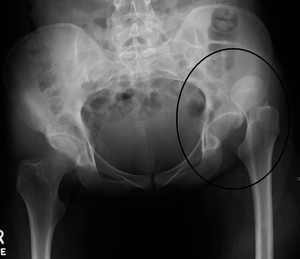

Dislocation of the hip is a common injury to the hip joint. Dislocation occurs when the ball–shaped head of the femur comes out of the cup–shaped acetabulum set in the pelvis. This may happen to a varying degree. A dislocated hip, much more common in females than in males, is a condition that can either be congenital or acquired.[1] Understanding the epidemiology, anatomy, difference between congenital and acquired, screening, treatments, and rehabilitation are all relevant to the topic.

The hip joint includes the articulation of the femoral head (of femur) and the acetabulum of the pelvis. In hip dislocation, the femoral head is dislodged from this socket. Posterior dislocation is the most prevalent, in which the femoral head lies posterior and superior to the acetabulum. This is most common when the femur is adducted and internally rotated. The opposite is true for the shoulder, where the most common dislocation occurs in the anterior and inferior directions.[1] The posterior side of the hip exhibits primarily hip extension, dealing with the muscles: gluteus maximus, hamstring muscles (biceps femoris, semitendinosus, semimembranosus), and the six deep external rotators (piriformis, obturator externus, obturator internus, gemellus superior, gemellus inferior, and quadrates femoris).[4]

Congenital hip dislocation

Congenital hip dislocation also known as dysplasia of the hip is a condition in which a child is born with a hip problem. Congenital hip dislocation is when the formation of the hip joint is abnormal. The ball at the top of the thighbone which is known as the femoral head is not stable within the socket (which is also known as the acetabulum). This abnormality may cause the ligaments of the hip to be loose or stretched. This condition is usually diagnosed once the baby is born; it mostly affects the left side of the hip in first-born children, girls, and babies born in a breech position. Girls are four times as likely to have hip dysplasia compared to boys. The cause of this condition is still unknown; however, some factors of congenital hip dislocation are through heredity and racial background. It is also thought that the higher incidence in some ethnic groups ( such as some Native American groups) is due to the practice swaddling of infants, which is known to be a potential risk factor for developing dysplasia. It also has a low prevalence risk in African Americans and southern Chinese. Native Americans are more likely to have congenital hip dislocation than any of the other races. The risk for Native Americans is about 25-50 in 1000. The overall frequency of developmental dysplasia of the hip is approximately 1 case per 1000 individuals; however, Barlow believed that the incidence of hip instability in newborns can be as high as 1 case for every 60 newborns.[7]